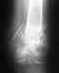

Пожалуйста, посмотрите снимок. Был проведен остеосинтез гвоздем. Гвоздь сломался. Сделали повторную операцию год назад. Перелом не сросся. Все блокирующие шурупы сломались. Что делать? Ждать, пока сломается очередной гвоздь? Если ли надежда на сращение? Спасибо заранее за ответы.